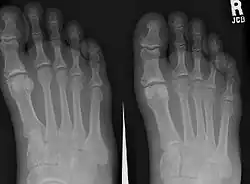

Człowiek ma pięć palców u każdej stopy, wyjątek stanowią osoby z polidaktylią czy syndaktylią. Palce stopy numeruje się od strony przyśrodkowej, tak że pierwszy numer otrzymuje paluch, składający się z dwóch kości (paliczków). Pozostałe palce stopy człowieka mają po trzy paliczki[1].